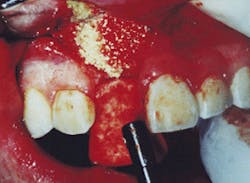

When grafting socket(s), primary closure cannot always be achieved. In these cases, epithelium begins to proliferate from the margins of the wound and migrate across at a rate of 0.5 mm per day. It can be assumed that in a period of 10 - 14 days enough granulation tissue will have been formed to cover the socket(s) and contain any graft material present. The period of concern is immediately following the placement of the graft until the time the natural healing response has covered the socket(s). Particulate graft material in itself will help prevent epithelial down-growth into the extraction socket, but a membrane is needed to aid in containing the graft material. This is in contrast to guided tissue regeneration (GTR), in which a true barrier membrane material is specifically designed to prevent epithelial down-growth for a longer period of time. Gelfoam® Sterile Sponge (Pharmacia & Upjohn, Kalamazoo, MI) is a medical device intended for application to bleeding surfaces as a hemostatic. Surface-acting hemostatic devices, such as Gelfoam, arrest bleeding by providing a mechanical matrix that facilitates clotting. Due to its bulk, Gelfoam slows the flow of blood, protects the forming clot, and offers a framework for deposition of the cellular elements of blood. It is a porous, pliable, sponge-like material that can be cut to size without fraying or losing its integrity. It is easily placed over fresh extraction sites, regardless of the size or configuration of the socket. Applied dry, Gelfoam can be compressed to adapt firmly to the socket walls (Figure 2). According to the manufacturer, Gelfoam will break down in approximately one week and is absorbed completely in four to six weeks. Gelfoam seems to maintain control of the site long enough for epithelization to contain the graft. It offers a protective cover and provides structural support for the reparative process. It is an inexpensive way to achieve containment of the OsteoGraf/LD-300 in the socket walls.

Figure 2